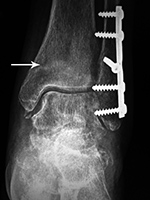

Left tibia stress fracture after fibular fracture fixation |

A short one-third tubular plate and screws plus interfragmentary screw stabilize a healing distal fibular fracture. An associated stress fracture (arrow) is in the distal tibial metaphysis from altered weight-bearing from the fibular fracture. |